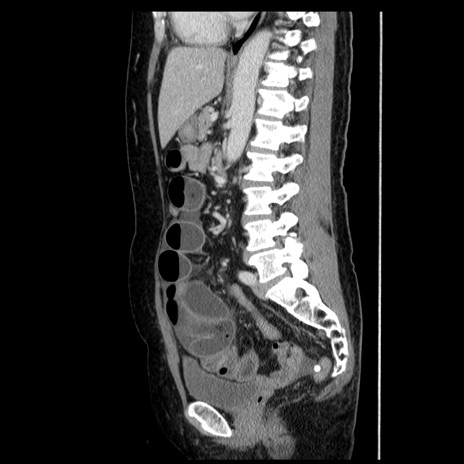

横断像